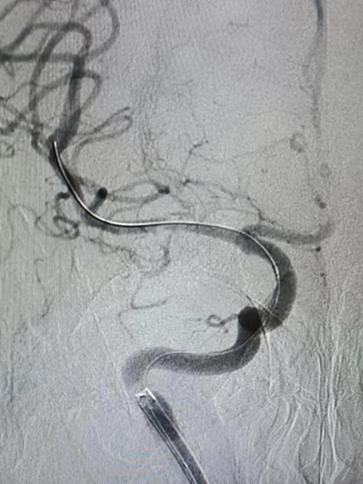

Guiding到位,导丝通过病变。

球囊通过病变。

球囊扩张过程。

扩张后造影。

支架通过病变。

支架释放。